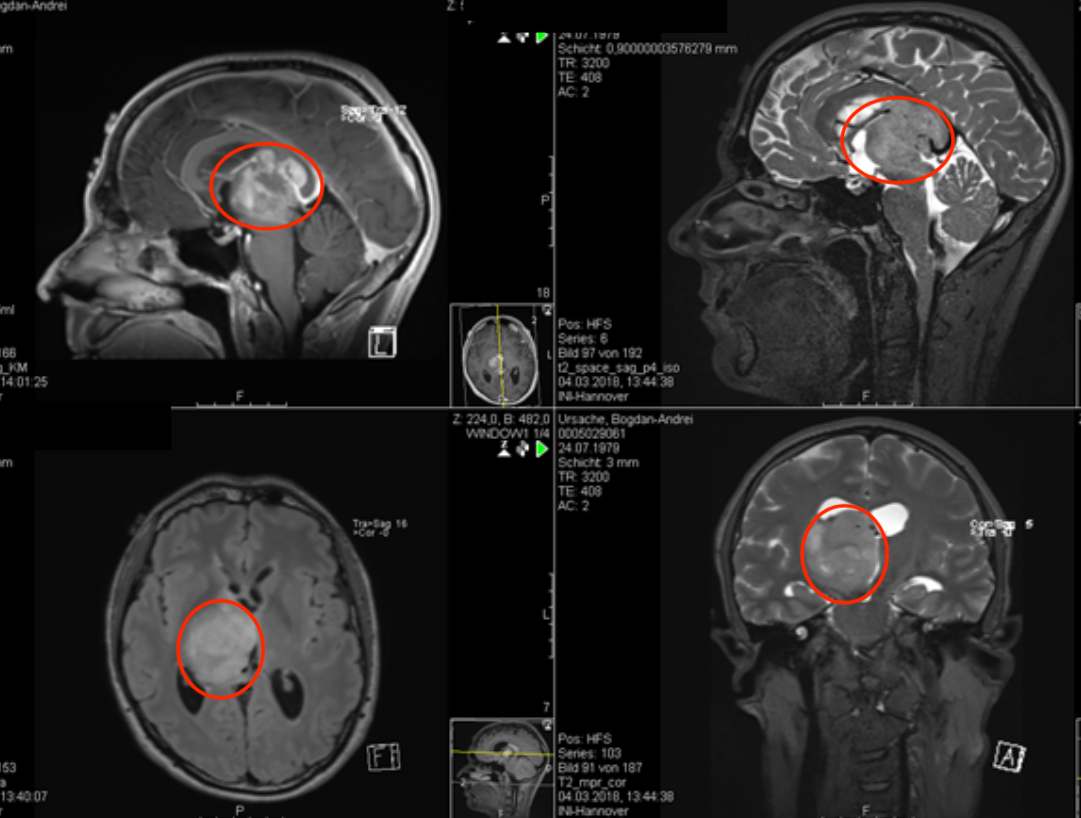

壓迫腦干的較大丘腦膠質瘤次全切手術報告

【較大丘腦膠質瘤次全切手術案例】簡要病史:39歲男士,在足球比賽中頭部輕微外傷后,患者于3個月前開始出現(xiàn)臨床癥狀,輕度復視,于是進一步的診斷檢查。 診斷:右側丘腦膠質瘤,壓迫...

丘腦膠質瘤的影像學研究與分類

磁共振成像(MRI)已經(jīng)成為鑒別和分類顱內(nèi)腫瘤的標準診斷工具...